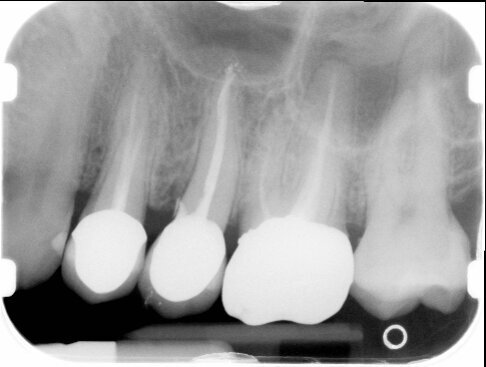

Avvenuta la fissazione degli elementi (Fig. 16), procediamo al controllo radiografico sempre con il centratore e laddove possibile si utilizza un gig in silicone che potrà riprodurre sempre la medesima sequenza proiettiva radiografica. Si possono comparare le immagini radiografiche iniziali e finali vedendo come all’apice del dente naturale sia modellato il confine con la parete del seno mascellare superiore (Fig. 2) con il rimodellamento che la stessa compie attorno all’impianto ad un anno dal carico (Fig. 17).

Fig. 2 - Radiografia endorale di controllo, eseguita con centratore.

Fig. 17 - Radiografia di controllo a 1 anno dal carico.